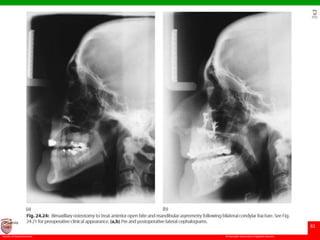

Bilateral condylar malunion

• results in anterior open bite and class II jaw relationship.

• The correction is achieved by adjusting the maxilla to

accommodate this reduced posterior face height by carrying

out a posterior maxillary impaction.

• This results in an increase of the occlusal plane angle, but

this is of little significance and will result in a stable

correction of the anterior open bite component of the

deformity, as a consequence of mandibular autorotation.